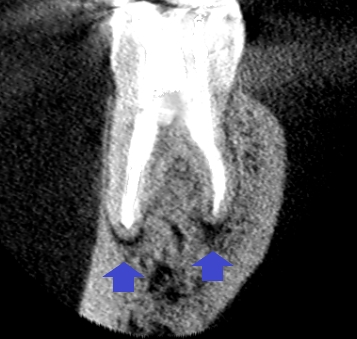

精密根管治療6ヶ月後の経過観察時の矢状断のCT画像です。青い矢印の先にあった膿の影が縮小し歯槽骨が再生してきています。